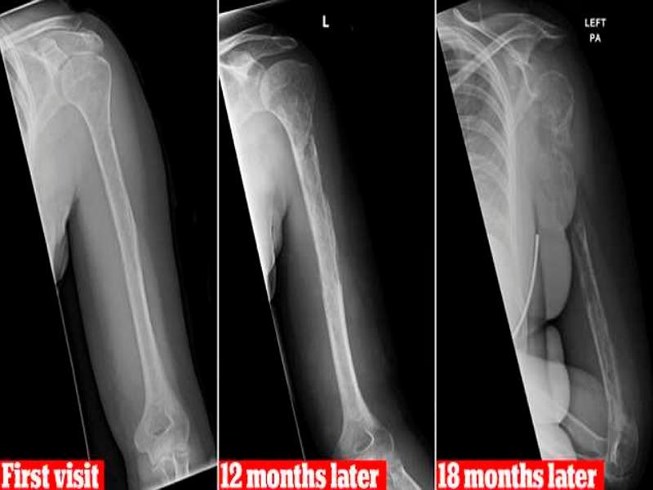

Các kết quả chụp Xquang theo thời gian. |

Bản chụp phim đầu tiên của bà cho thấy bà có 1 tổn thương trên xương cánh tay trên, ban đầu bác sĩ nghĩ là ung thư, nhưng xét nghiệm lại không phải.

7 tháng sau, bệnh nhân trở lại bệnh viện, xét nghiệm cho thấy có khối u mạch máu lành tính.

18 tháng sau, bản chụp phim cho thấy xương của bà đã biến mất. Cả phần xương cánh tay trên và xương ở mu bàn tay của bà đã mất dấu trong phim chụp, được thay thế bằng các mạch máu ở chỗ mô xương.